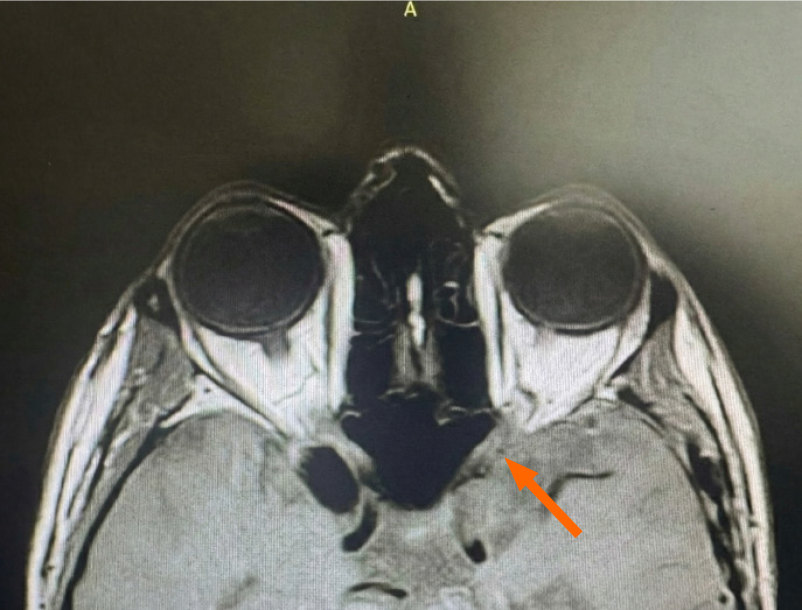

Urgent MRI of the brain and orbits with contrast revealed a T1-hyperintense, fat-containing lesion within the left anterior clinoid process of the sphenoid bone at the level of the optic canal, causing significant extrinsic compression of the left optic nerve (Figure 2). The lesion demonstrated signal characteristics compatible with adipose tissue on fat-sensitive sequences. No additional intracranial mass, acute ischemia, or hydrocephalus was identified.

These findings were most consistent with an intraosseous lipoma of the sphenoid/anterior clinoid process compressing the optic nerve, while acknowledging that other fat-containing lesions (e.g., dermoid cysts or lipomatous variants) can have overlapping imaging features.